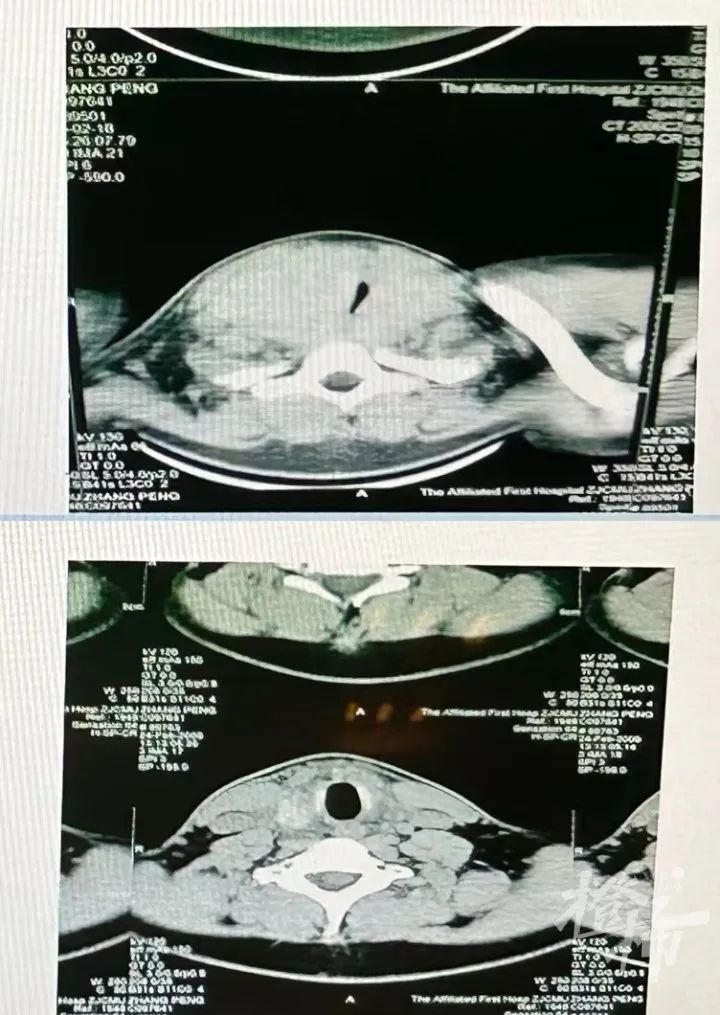

20岁的小雨也有类似的经历,他比小玲的情况更严重,他来医院时吐气都很困难,睡觉时出现了严重的打呼声,甚至影响到了在隔壁睡觉的父母。通过甲状腺B超检查,小雨的气道被甲状腺肿瘤严重压迫。“原本通畅的气道被压迫到只剩一道极窄的缝隙,所以他才会出现吐气困难、打呼严重的情况。”傅教授说。手术后,小雨终于恢复正常,能够顺畅吐气了。

▲小雨手术前后的气道对比图。(医院供图)